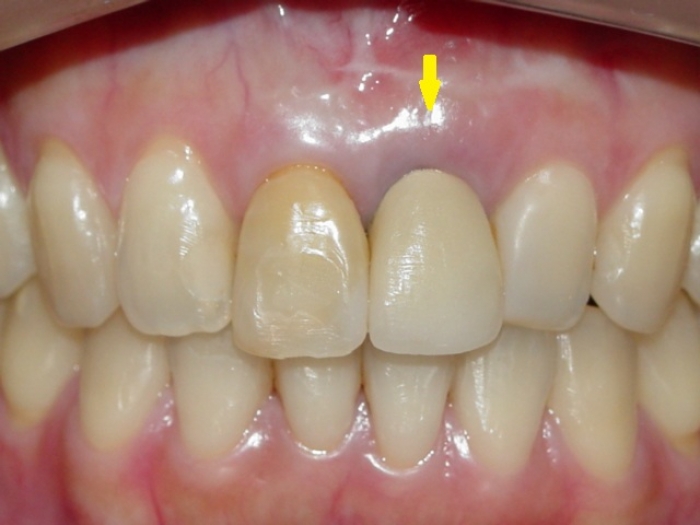

Imagens iniciais com elemento 21 comprometido